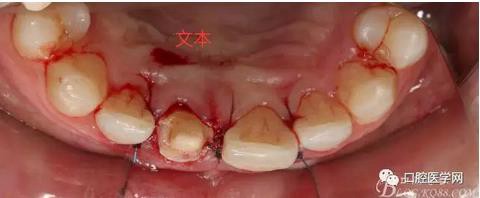

翻瓣 見11釉牙骨質(zhì)界存在,牙槽嵴頂?shù)接匝拦琴|(zhì)界不足2mm。21牙槽嵴頂?shù)接匝拦琴|(zhì)界不足2mm

去骨后,牙槽嵴頂?shù)接匝拦琴|(zhì)界達到2.5mm。保留11,21之間的牙槽嵴頂,不改變齦乳頭的狀態(tài)。